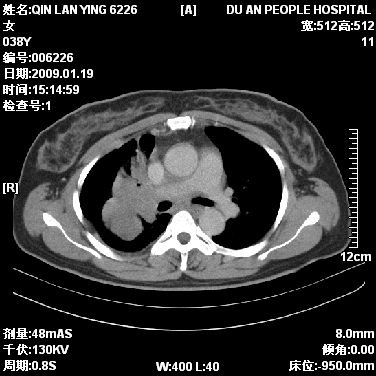

女,38岁,胸疼1个月。wbc:1万4

1)右肺中央型肺癌并右肺上叶阻塞性肺炎、节段性肺不张,纵隔淋巴结转移、右侧胸膜转移、肝脏转移。2)右侧胸腔少量积液。

1、右侧中央型肺癌并阻塞性肺不张,纵隔内、主动脉弓旁、右肺门淋巴结及肝脏转移可能性大,建议纤支镜进一步检查。

2、右侧胸腔积液。

本病例有几个容易诊断的地方:1、右肺上叶前段支气管闭塞,肺不张。2、淋巴结明显肿大。3、肝脏多个类圆形低密度影呈“牛眼征”改变,高度提示转移。

从影像学角度分析      右肺上叶中央型肺癌,并阻塞性不张、肺炎,纵隔淋巴结、膈顶淋巴结转移。